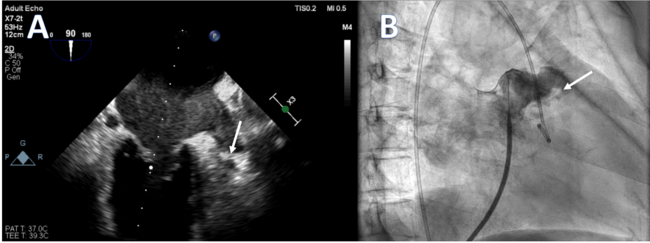

Fibrillatory Left Atrial Appendage With Tip Clot